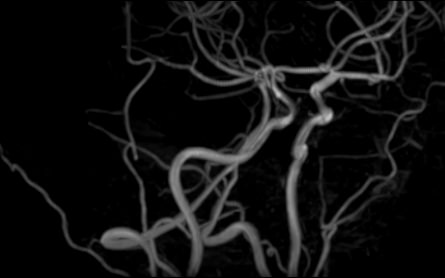

Исследования выполняются на современном высокопольном томографе экспертного класса TOSHIBA VANTAGE TITAN 1,5 Тесла, который использует разные режимы сканирования с толщиной среза от 1мм в различных плоскостях с последующей цифровой обработкой полученных данных для создания трехмерных изображений. МР-ангиография отображает состояние артериальной системы кровоснабжения головного мозга. МР-венография головного мозга позволяет детально изучить особенности венозного русла головного мозга.

Компьютерная программа обрабатывает данные, полученные при сканировании, и формирует объемные изображения как самого мозга, так и сосудистой системы в отдельности без прилегающих тканей. Методики применяются одновременно и взаимодополняют друг друга.

• патология нервов на фоне сосудистых проблем (вазоневральный конфликт — сдавление нерва близлежащим сосудом, также на фоне патологической извитости, аневризмы, сосудистой мальформации).